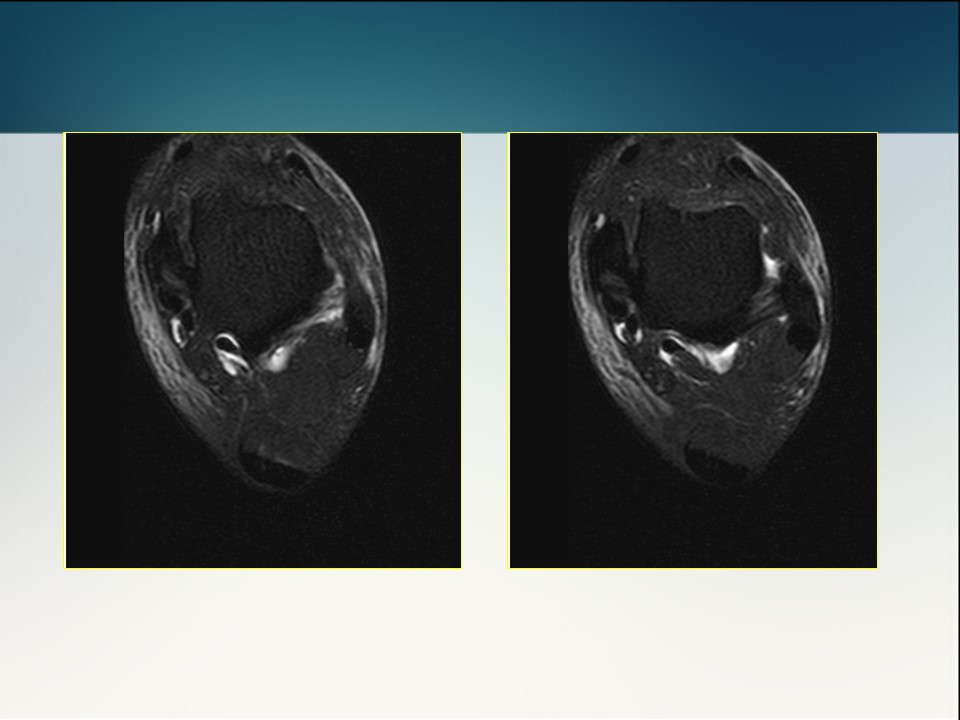

半月板损伤术前及修补术后MR影像学评价